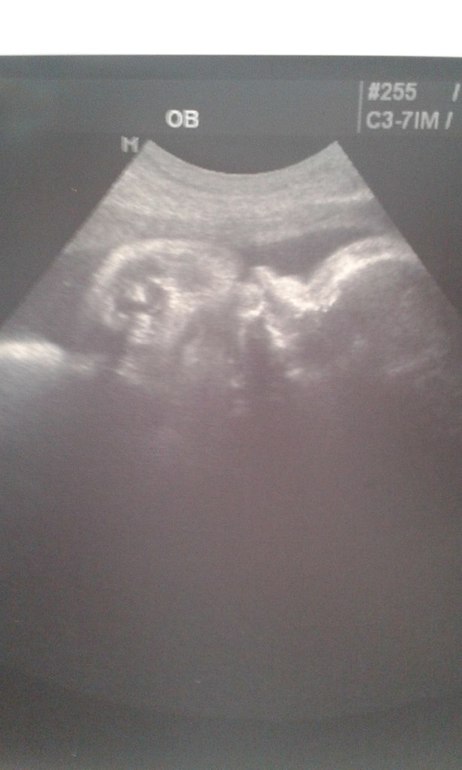

А вот и ее домик:

1. Все внутренние органы (даже почки, которые в начале беременности были с пиелоэктозией) в норме и соответствуют сроку 36 недель. ЧСС - 143 уд в минуту (малышка пинала датчик, поэтому не сразу удалось померить число ударов)

2. Весим уже 2800 г (ого-го, какие мы уже большие, а в 30 недель весили 1330г). Но врач сказала, по росту мы родимся небольшими (значит проще рожать будет).

3. Воды в норме - и количество и качество.

4. Плацента уже 3 степени и врач сказала, что я могу еще две недельки походить ( но малышка уже готова к родам - легкие в норме и она, если родится сейчас, то сможет сама дышать)

5. Провели и диагностику ШМ с зевом (как то вагинально мне было больнова-то) - 41*36 мм, зев закрыт.

Все она мне показывала и рассказывала, было очень интересно. И показали наше личико, такая она сладенькая - губки бантиком (что-то сначала причмокивала, а потом стала пальчики сосать - видимо они очень вкусные

), носик курносый, пухлые щечки - прям красотка))) Я даже не знаю на кого она похожа - видимо на себя саму

(жаль, что длилось это удовольствие 20 минут). Красотка моя не захотела нормально фоткаться и поэтому удалось сфотографировать с пальчиками во рту: